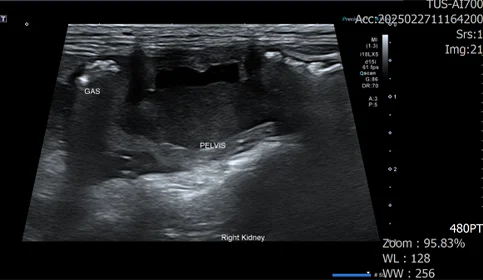

• 세균성 신우신염 및 신장파열 환자

식욕 부진과 체중 감소로 내원한 환자입니다.

혈액 검사상 WBC 상승, 신장 수치 상승, 심각한 수준의 전해질 불균형이 확인되었습니다.

우측 신장 주변부 가스, 복수, 신장의 형태 변화, 신우의 확장, 요관 확장 확인

신우내 저류하는 액체 천자 진행, 점액성 농이 다수 확인

도말 상 세균 확인

정밀 검사 결과, 신장 주변 가스, 복수, 신장 파열이 확인되었습니다.

세균성 신우신염으로 인한 신장 파열이 발생, 그로 인한 이차적인 복막염으로 진행되는 상태입니다.

즉시 우측 신장절제 수술을 진행했으며, 입원 기간 동안 쇼크와 빈혈 등 수많은 응급 상황이 발생했으나 매 순간 적절한 처치와 항생제 치료를 통해 환자 상태가 호전되었습니다.

15일 만에 신장 수치 정상화 후 무사히 퇴원했습니다.